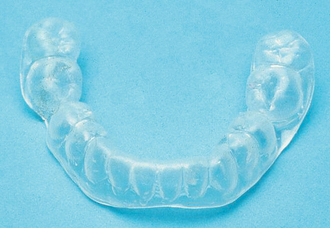

A common second line is the soft vinyl mouthguard (Fig. 16.1), which, although claimed by some to worsen bruxism, does appear to work for many patients and is both inexpensive and simple to construct, requiring only one lower impression. The author recommends this appliance for night use only, for about 6 weeks: as it cannot be adjusted precisely to the occlusion, wearing the appliance 24 hours per day does result in uneven tooth movement. If it has not brought any improvement in 6 weeks, the likelihood of success is small and its use should be discontinued. Many other designs of appliance are used for this condition and it is beyond the scope of this book to review them all. The occlusally balanced or stabilization appliance is a rigid acrylic device made to fit closely into the occlusal surfaces of both upper and lower teeth when the jaw is held in a retruded position with the teeth marginally apart. It may be retained with clasps or ball cleats attached to the teeth. It can be worn all day, but there is little evidence that results are better than that achieved by night use only.

image

Fig. 16.1 Soft lower splint.